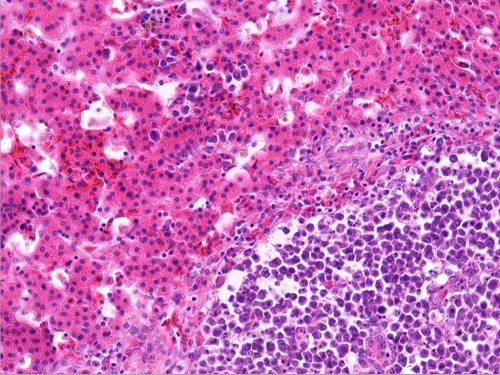

鳞状上皮细胞癌1(10X40)

鳞状上皮细胞癌2(癌巢之间为纤维结缔组织和较大的血管10X40)